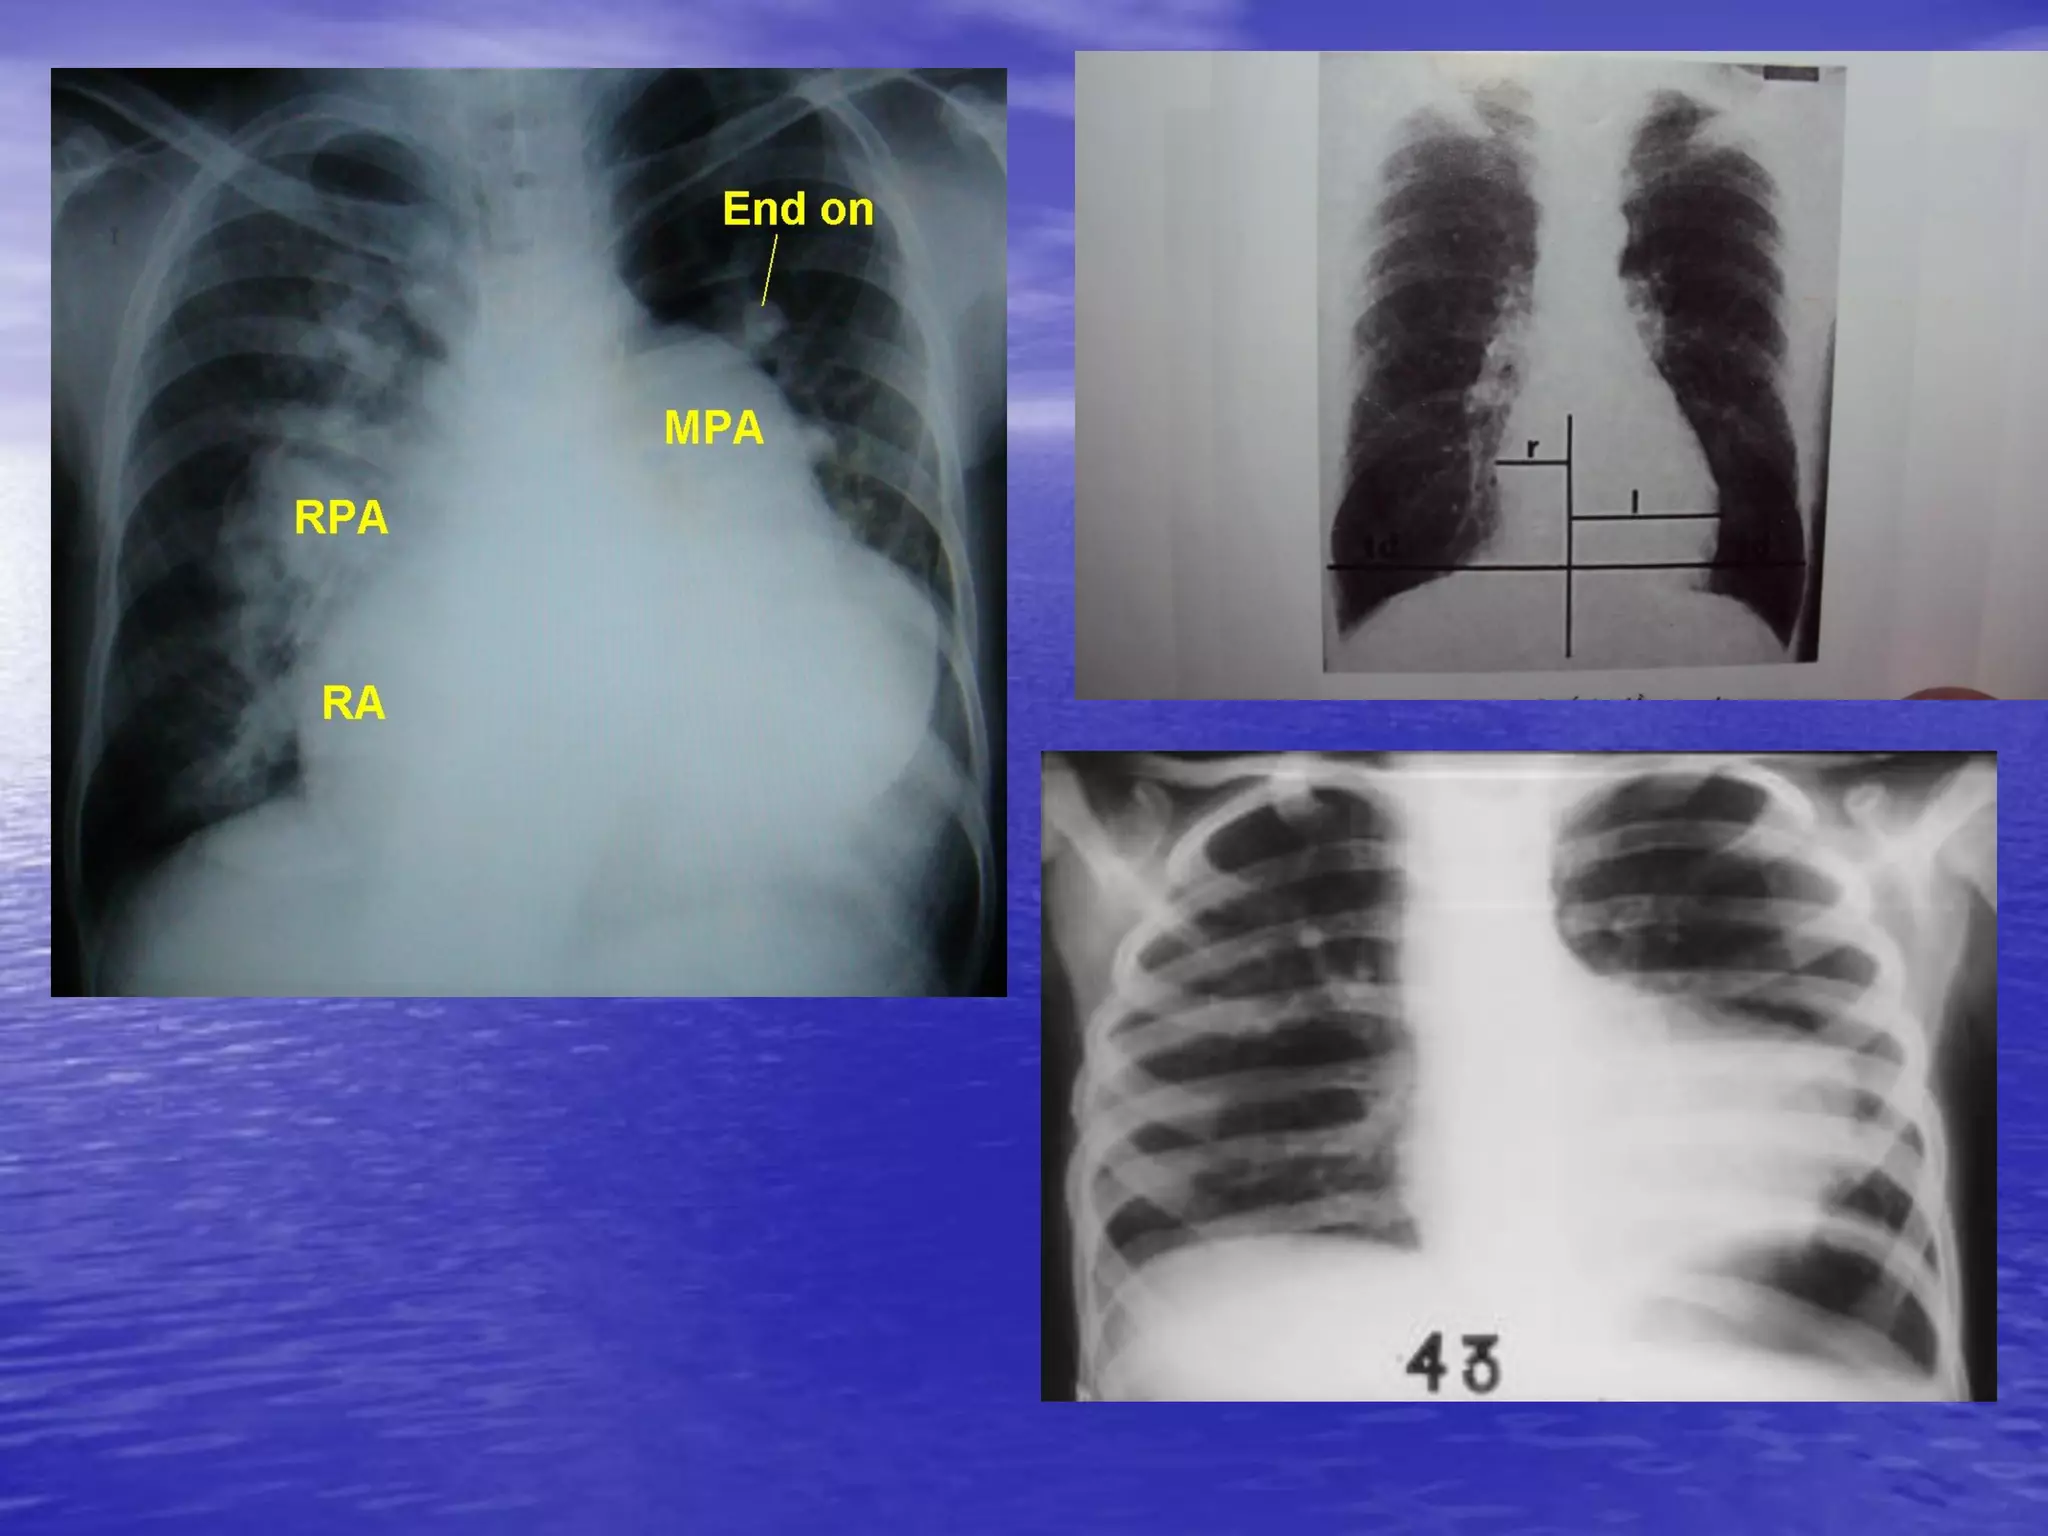

Tuần hoàn phổi / XQ ngực

• Tăng tuần hoàn phổi trung tâm và giảm ở ngoại

biên

– Biểu hiện

• ĐMP tăng ở trung tâm va giảm đột ngột ở ngoại biên

• Phế trường tăng sáng

• Cung ĐMC nhỏ

– Nguyên nhân:

• Tăng áp ĐMP nguyên phát

• Hội chứng Eisenmenger

• Tâm phế mạn tính

• Thuyên tắc ĐMP tái diễn

• Hẹp 2 lá lâu năm

Tuần hoàn phổi/ XQ ngực • Tăng tuần hoàn phổi trung tâm và giảm ở ngoại biên – Biểu hiện • ĐMP tăng ở trung tâm va giảm đột ngột ở ngoại biên • Phế trường tăng sáng • Cung ĐMC nhỏ – Nguyên nhân: • Tăng áp ĐMP nguyên phát • Hội chứng Eisenmenger • Tâm phế mạn tính • Thuyên tắc ĐMP tái diễn • Hẹp 2 lá lâu năm